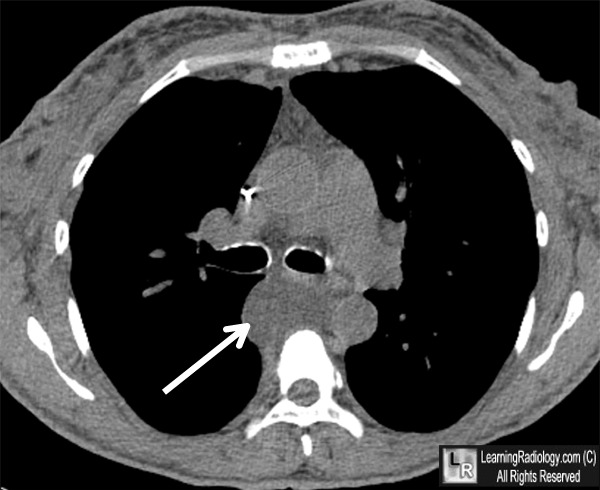

Mediastinal duplication cyst ct